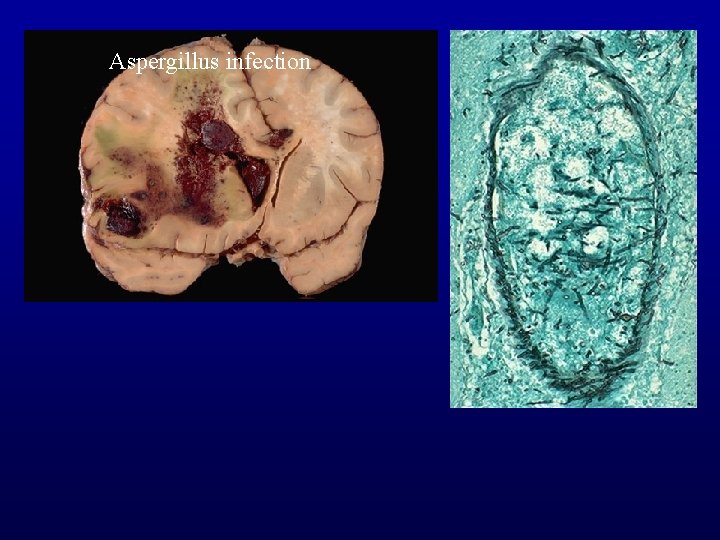

Aspergillus infection

MUCOR • Infects the sinuses of diabetic patients with ketoacidosis – • with direct invasion of the orbits and CNS (rhinocerebral mucormycosis) Mucor has a propensity for – – vascular invasion with secondary thrombosis hemorrhagic cerebral infarction

Opportunistic CNS Infections Associated with AIDS Viral Infections: Autopsy Incidence Subacute (HIV) Encephalitis 28% CMV Encephalitis 26% Nonspecific Encephalitis 17% Progressive Multifocal Leukoencephalopathy 2% Varicella-Zoster Encephalitis 2% Herpes Simplex Encephalitis 2% Fungal Infections: Aspergillus 1% Candida 1% Cryptococcus 3% Histoplasmosis 1% Parasitic: Toxoplasmosis 10% Neoplasms: Primary CNS Lymphoma 6%